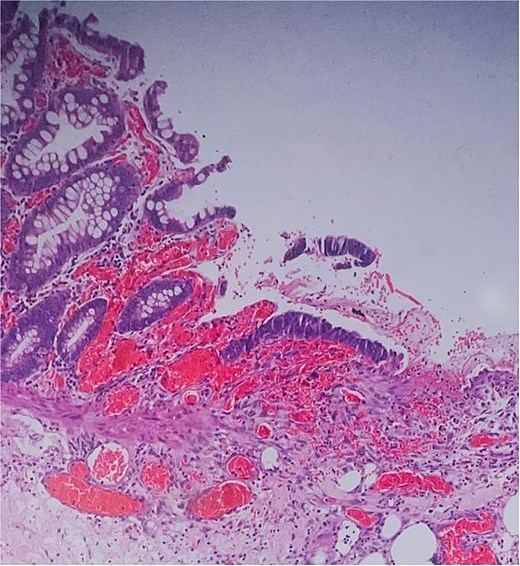

Histological evaluation confirmed acute necrotizing colitis with transmural inflammation and granulation tissue (Figs 4 and 5). Hepatic cyst biopsies revealed benign biliary duct cysts with cystically dilated bile ductules.

Histopathology: surface ulceration with perforation as indicated by fat lobules (arrow).